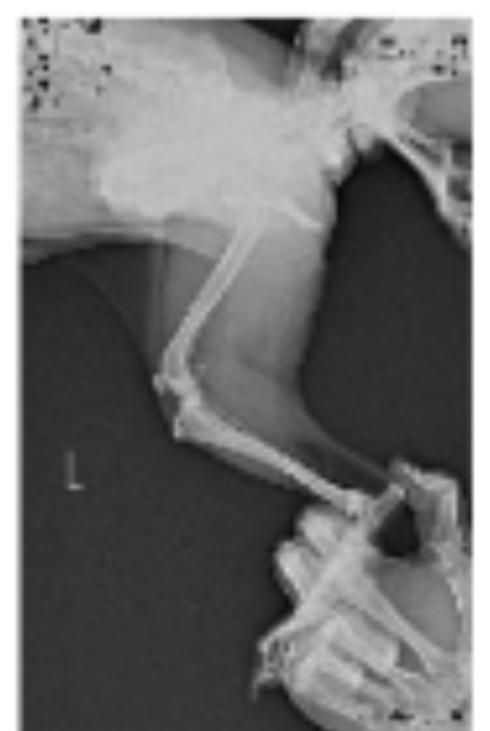

강아지 엑스레이 슬개골 탈구랑 십자인대 봐주세요ㅠㅠ

저희집 강아지가 공놀이를 좋아하고 산책할때 좀 흥분해서 뛰는 편입니다ㅠㅠ 그래서 어릴때부터 슬개골이 좋지는 않고 1기에서 2기로 진행되고 있다는 얘기는 왕왕 들었는데 항상 꼬리를 들고 있는 앤데 꼬리도 내려가고 오른쪽 다리를 아파하는거 같고 산책나가서도 앉고 안걸을려고 해서 병원을 갔는데 슬개골 탈구랑 십자인대도 좀 안좋은거 같다고 영상기기 있는 곳애 가보라고 하셔서 가서 엑스레이를 찍어봤습니다..

엑스레이 한번만 봐주실 수 있나요ㅠㅠ

슬개골 탈구는 원래 엑스레이로 진단하는 질환이 아니라 주치의의 촉진으로 진단하는 질환입니다. 엑스레이는 이차적 혹은 별도로 십자인대의 이상이나 골절, 주변 연부조직, 관절면 등 유사한 증상을 보일 수 있는 동반 질환을 감별하기 위한 검사이기에 슬개골 탈구 자체의 진단에는 필수적인 검사는 아닙니다.